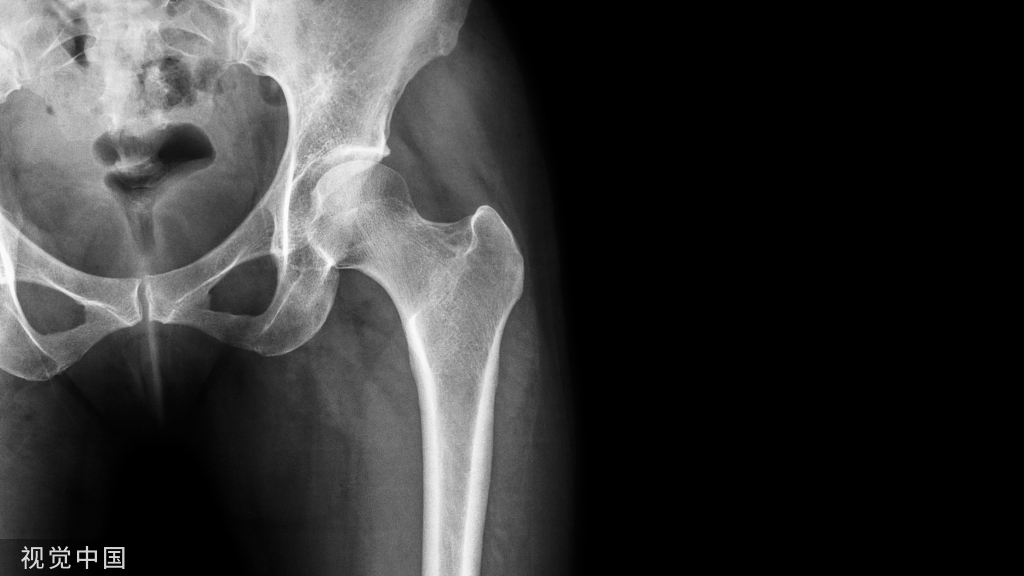

中国老年髋部骨折围术期护理专家共识(2023)发布

我国即将进入中度老龄化社会,骨质疏松相关的老年髋部骨折成为医疗机构面临的重大公共卫生挑战。老年髋部骨折患者由于各系统生理储备下降,多病共体,同时伴随多种老年综合征,围手术期护理面临巨大挑战,易出现疼痛、谵妄、营养不良、静脉血栓栓塞、尿潴留、衰弱、低体温、感染等多种问题。优化老年髋部骨折围手术期照护路径,减少并发症,降低病死率,改善老年髋部骨折患者健康结局是当前研究的重点和热点。但当前老年髋部骨折患者围手术期护理实践尚存在很多不规范之处,因此,此共识的制定旨在为老年髋部骨折患者围手术期护理提供科学、规范的实践标准,以期为老年髋部骨折患者的优质和同质化护理提供更多的借鉴与思考。

2023年5月,由骨科加速康复外科联盟和北京护理学会骨科专业委员会牵头、组织全国老年创伤护理专家制定的《中国老年髋部骨折围手术期护理专家共识》在《中华创伤骨科杂志》正式发表。该共识凝聚了多学科专家的力量,包括骨科、老年科、护理团队、麻醉科、营养科、康复科等的参与制定。依托骨科加速康复外科联盟、北京护理学会骨科专业委员会、中华医学会骨科学分会护理学组、中华医学会创伤学分会护理学组,在全国多位知名老年创伤骨科护理专家的共同努力下,该共识于2023年5月发表。共识贯穿老年髋部骨折围手术期护理、早期康复和出院管理等全程管理,给出了38条推荐意见。结合ERAS理念,优化老年髋部骨折患者整体护理,给老年髋部骨折患者带来更多的获益。